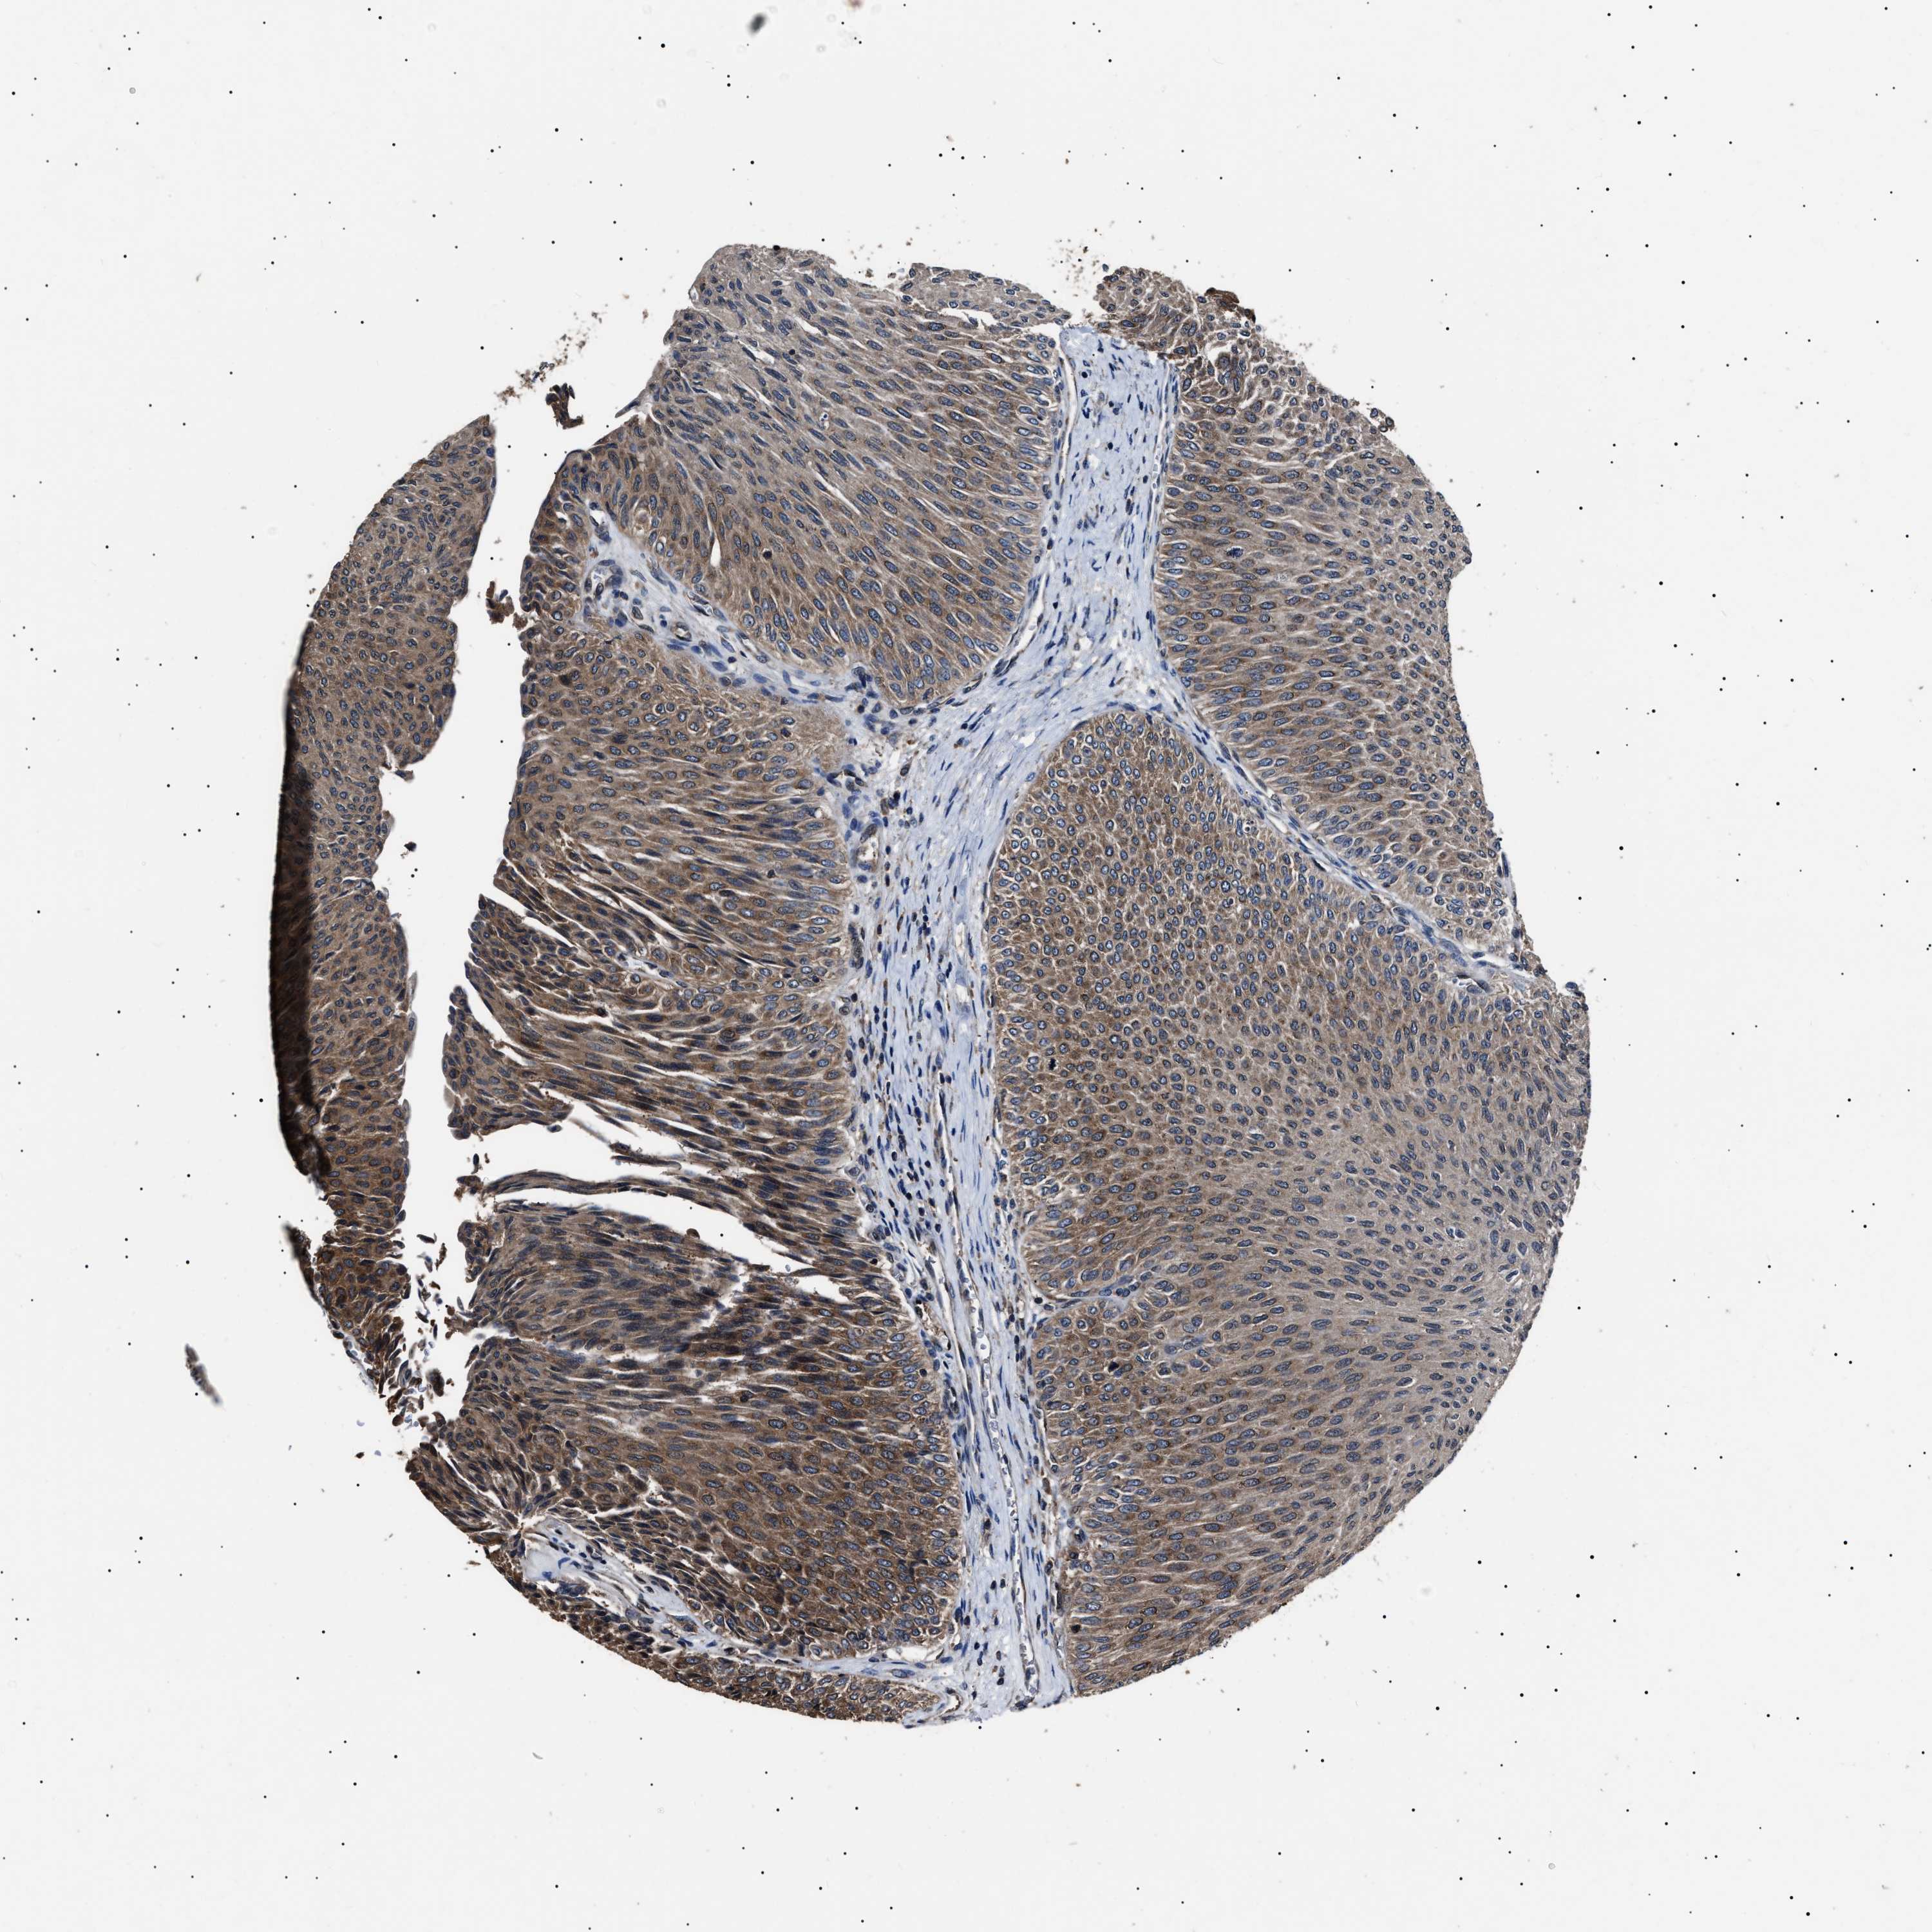

UROTHELIAL CANCER - Protein expressioni

A mouse-over function shows sample information and annotation data. Click on an image to view it in a full screen mode. Samples can be filtered based on level of antibody staining by selecting one or several of the following categories: high, medium, low and not detected. The assay and annotation is described here.

Note that samples used for immunohistochemistry by the Human Protein Atlas do not correspond to samples in the TCGA dataset.

Antibody stainingi

Antibody staining in the annotated cell types in the current human tissue is reported as not detected, low, medium, or high, based on conventional immunohistochemistry profiling in selected tissues. This score is based on the combination of the staining intensity and fraction of stained cells.

Each image is clickable and will lead to virtual microscopy that enables deeper exploration of all samples and also displays staining intensity scores, fraction scores and subcellular localization as well as patient and tissue information for each sample.

Antibody HPA018520

Antibody HPA021051

Antibody HPA029426

Urothelial carcinoma, Low grade

Urothelial carcinoma, High grade